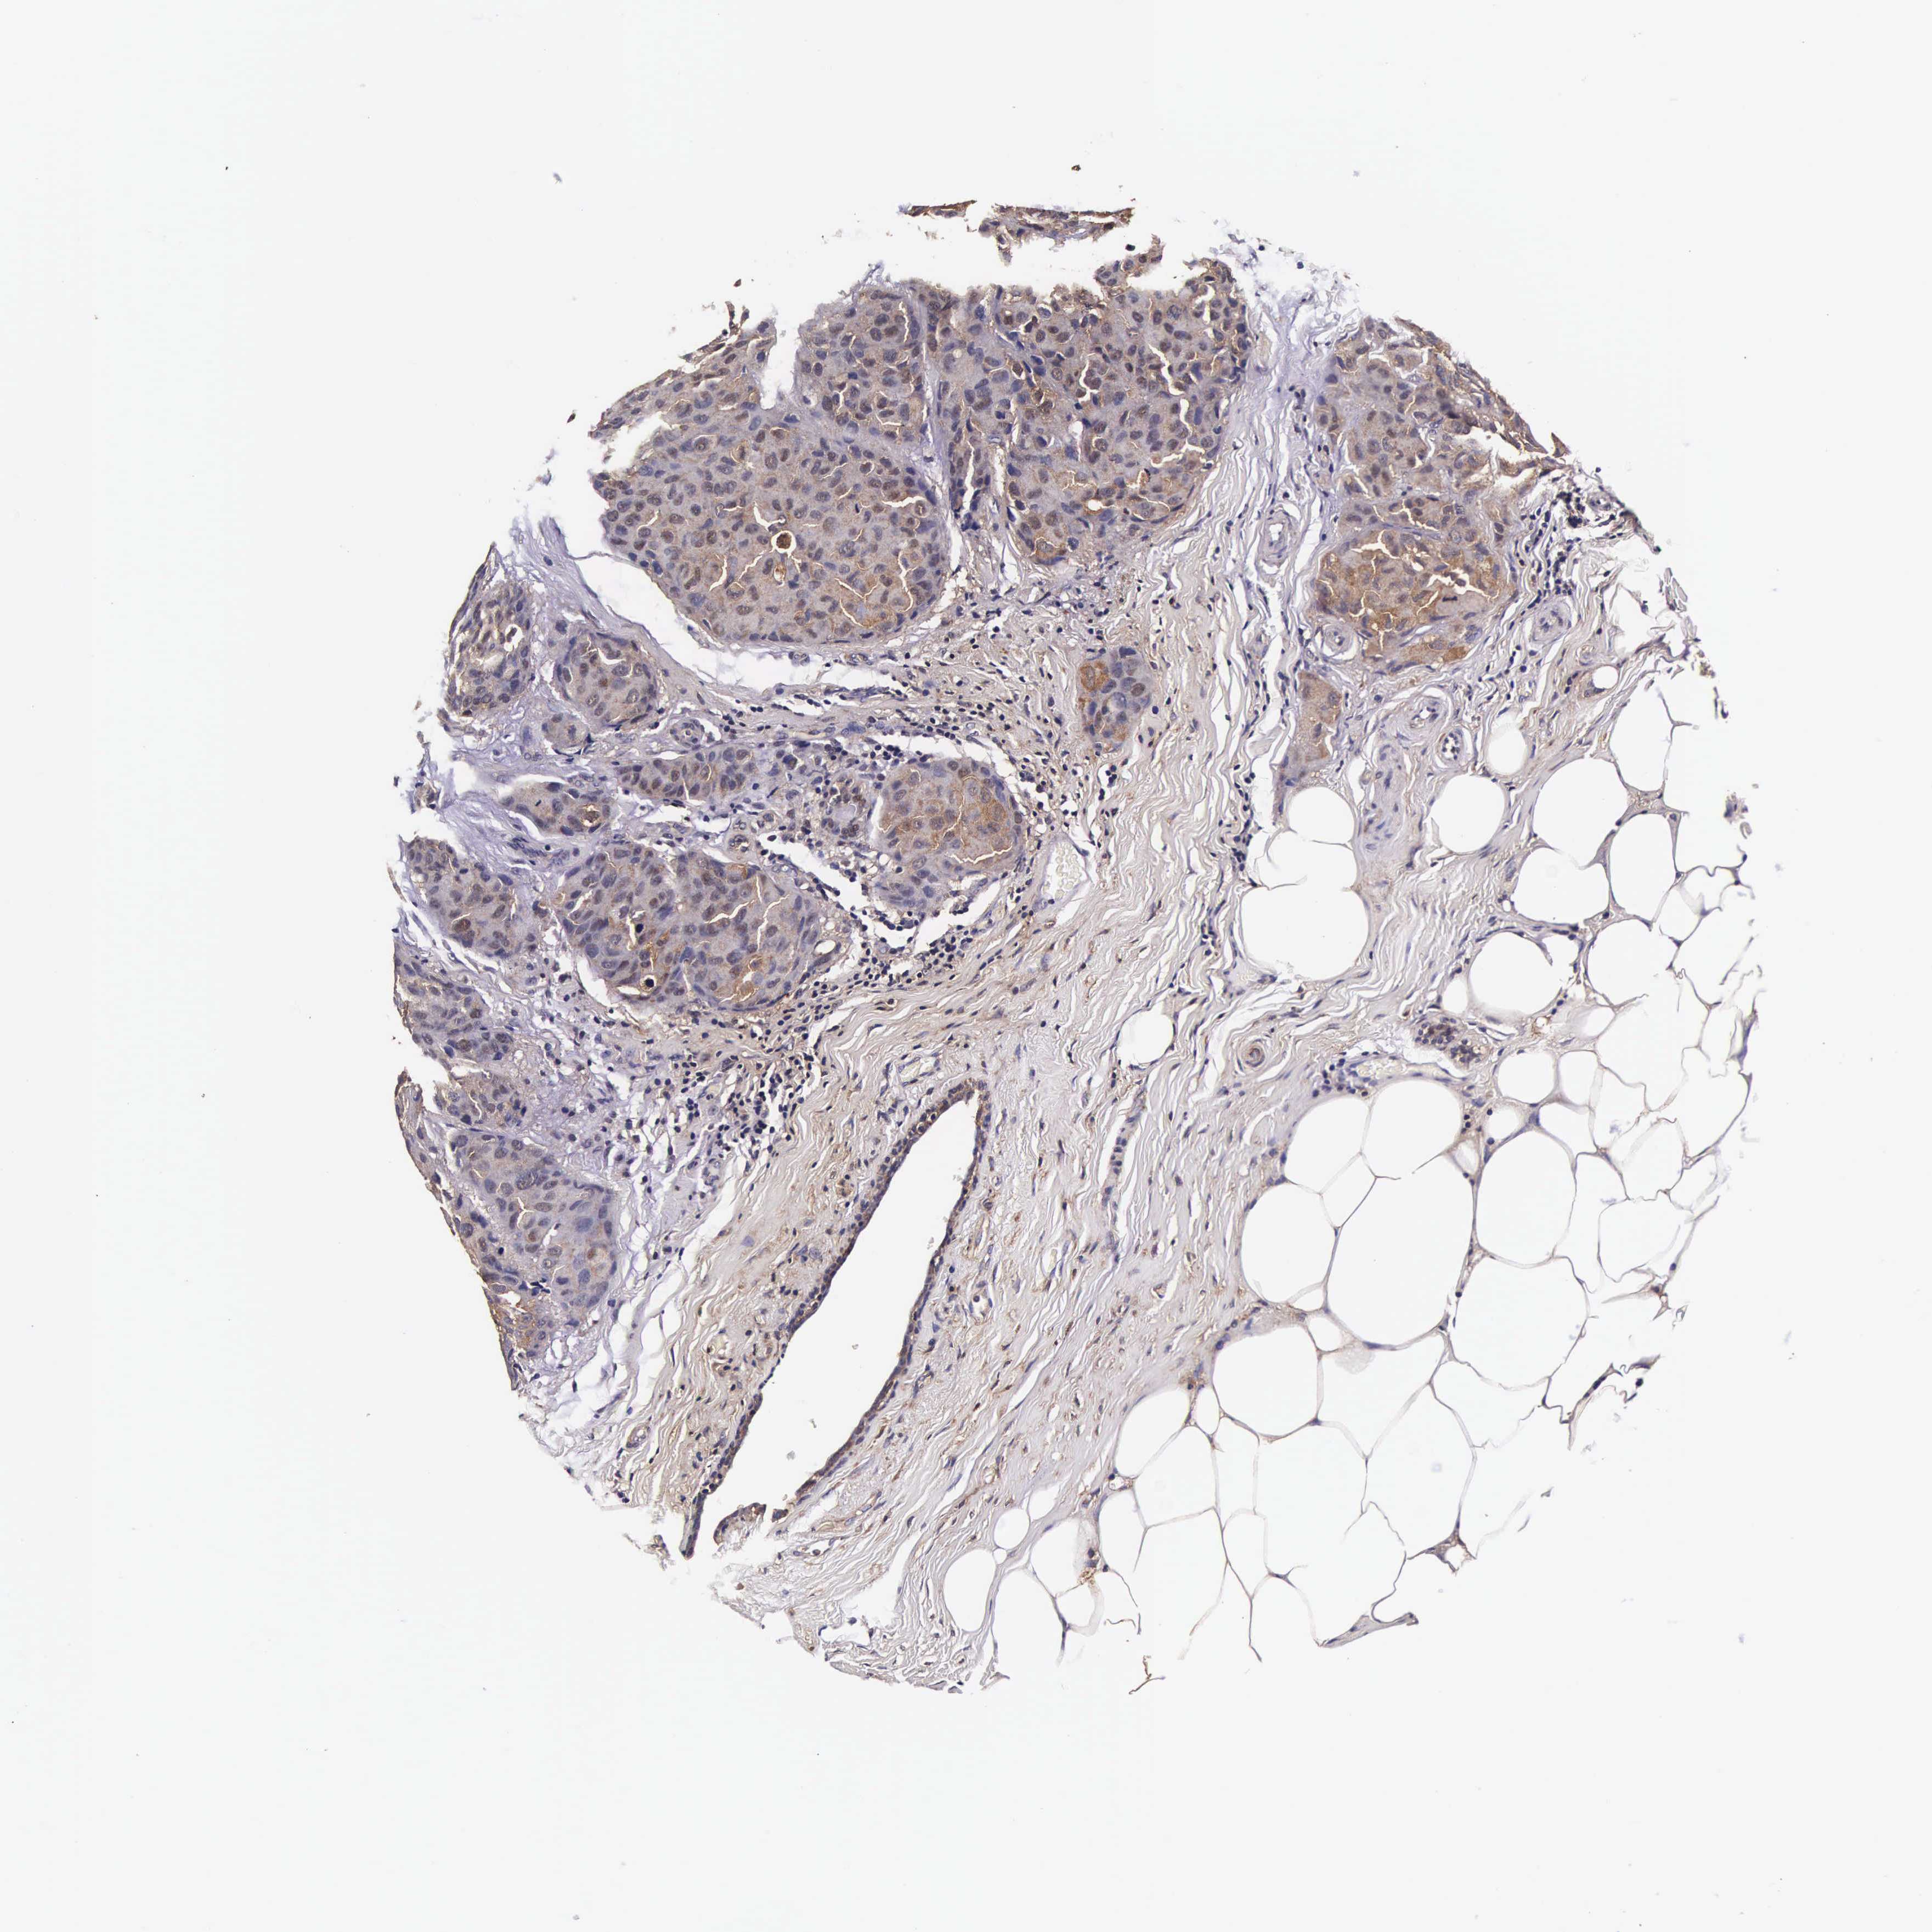

CANCER BREAST CANCER Show tissue menu

Breast cancer

Human cancer